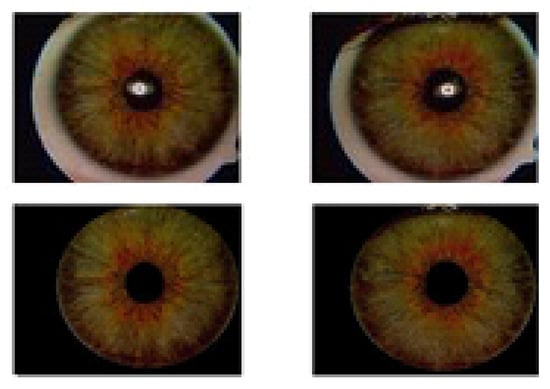

2. Image Database

4.4. Iris Image-Region Analysis